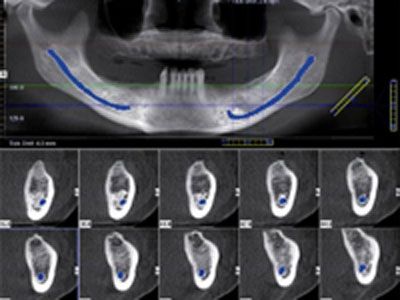

Planung von Implantaten

Die hochauflösenden Bilder zeigen

vollständige dreidimensionale Ansichten kritischer

anatomischer Strukturen. Dies ermöglicht die exakte Analyse

der Knochenstrukturen für die optimale Implantatplatzierung

und -versorgung.

Dazu gehört die Auswahl des am besten geeigneten Implantats

nach Typ, Größe und Position schon vor dem chirurgischen

Eingriff.